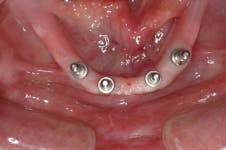

All-on-4 advocates claim that this type of treatment plan reduces cost and saves treatment time, but with the introduction of the ScrewIndirect one-piece implant that provides the implant, abutment, comfort cap, and transfer at a fraction of the cost of the implant alone from all the major implant companies, the economics argument for using the minimum number of implants is no longer valid. The ScrewIndirect screw-receiving platform allows splinting of implants that have up to 40 degree divergence, allowing distal angulations of up to 20 degrees if desired. Placement of five implants in the lower symphysis and six anterior to the maxillary sinuses can be relatively straight and still support adequate length of distal cantilevers. Four ScrewIndirect implants can also be placed, as shown below, splinted with a distal attachment for retention of an overdenture, but providing the patient with a fixed-detachable prosthesis that eliminates the need for a removable prosthesis is a more natural solution to restoring an edentulous jaw.